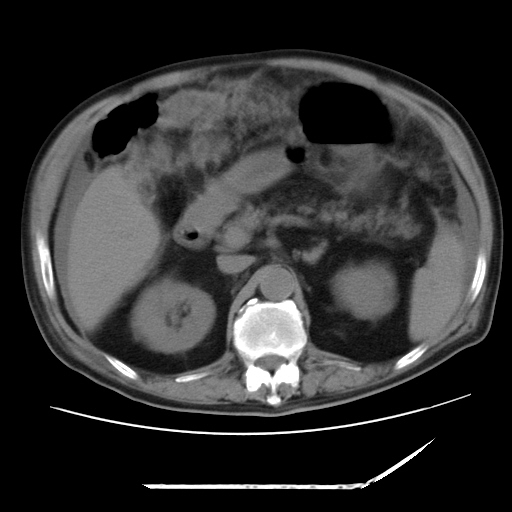

以下是引用zxl51642在2009-8-12 18:55:00的发言:[br]1、肠系膜脂肪浑浊,密度增高,腹水,支持腹膜炎诊断;2、右肾盂及输尿管中段结石,左输尿管起始段结石;3、胆囊切除术后改变?4、双侧胸膜腔少量积液;5、胰腺体积不大,勾勒清楚,肾前筋膜无增厚,不支持胰腺炎,请结合血尿淀粉酶及临床。